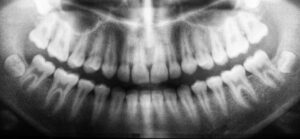

What are Wisdom Teeth?

Wisdom teeth are your third set of molars, usually emerging in late adolescence or early adulthood. They are named “wisdom teeth” because they develop at a more mature age compared to other teeth.

While some people experience no issues with their wisdom teeth, many others face complications due to lack of space or improper eruption, which can affect surrounding teeth and tissues.